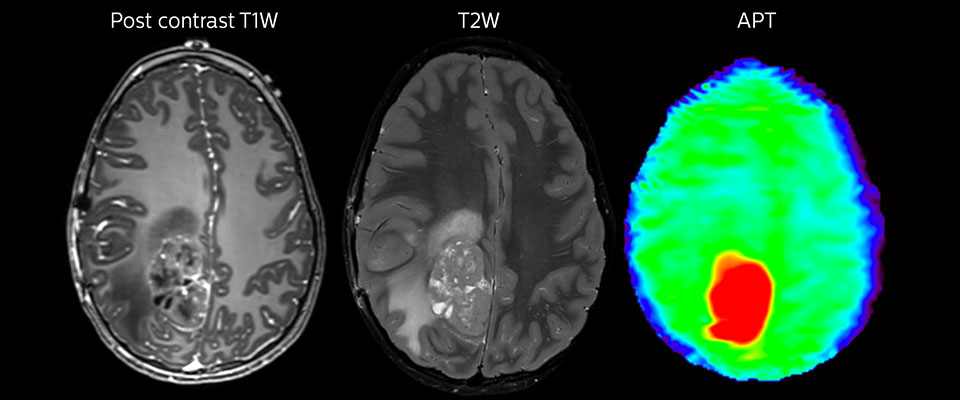

Large metastatic brain lesion

This 10-year-old patient underwent Ewing’s sarcoma tumor resection 7 years ago, but was found to now have a large metastatic lesion in the brain. This lesion shows clearly increased APT signal.

MRI with APT post resection

Immediately post resection MRI was again performed. T2-weighted and postcontrast T1-weighted images are quite inconclusive for distinguishing residual tumor tissue from postoperative tissue changes. On the APT image some high signal is still seen, which would suggest residual tumor tissue.

Follow-up over time

In later follow-up scans the post-contrast T1-weighted images suggest recurrent tumor growth. So, it would be interesting to study the predictive value of APT in a large patient group.